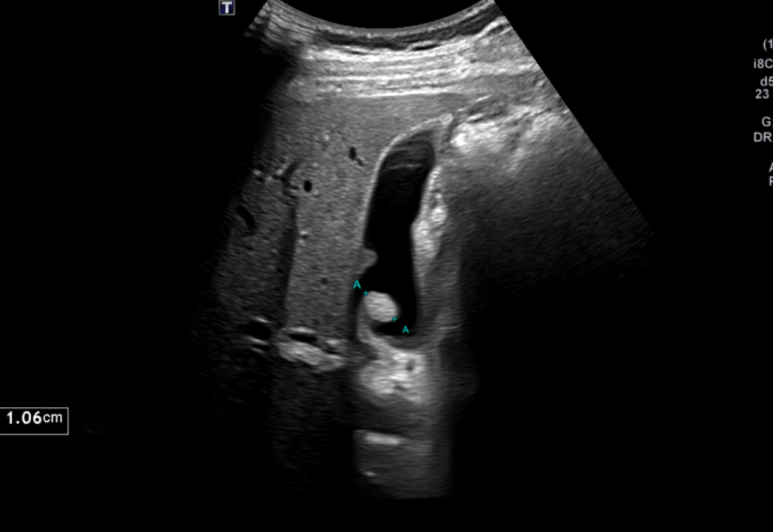

초음파로 간·담낭·담도·췌장·비장·신장·대동맥 등 복부 장기를 평가하는 비침습 검사입니다.

1. 담석증 & 담낭염

기름진 음식 후 우상복부 통증, 등이나 어깨로 방사, 구역구토가 흔하며, 염증이 생기면 고열심한 통증복부 압통이 동반됩니다.